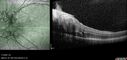

Albinism and Renal failure - Possible Hermansky-Pudlak Syndrome72 views65 year old female with foveal hypoplasia and renal failure since age 18. VA 20/40 OD, 20/63 OSDec 21, 2024

Albinism and Renal failure - Possible Hermansky-Pudlak Syndrome66 views65 year old female with foveal hypoplasia and renal failure since age 18. VA 20/40 OD, 20/63 OSDec 21, 2024

Albinism and Renal failure - Possible Hermansky-Pudlak Syndrome73 views65 year old female with foveal hypoplasia and renal failure since age 18. VA 20/40 OD, 20/63 OSDec 21, 2024

Albinism and Renal failure - Possible Hermansky-Pudlak Syndrome83 views65 year old female with foveal hypoplasia and renal failure since age 18. VA 20/40 OD, 20/63 OSDec 21, 2024

Albinism and Renal failure - Possible Hermansky-Pudlak Syndrome79 views65 year old female with foveal hypoplasia and renal failure since age 18. VA 20/40 OD, 20/63 OSDec 21, 2024